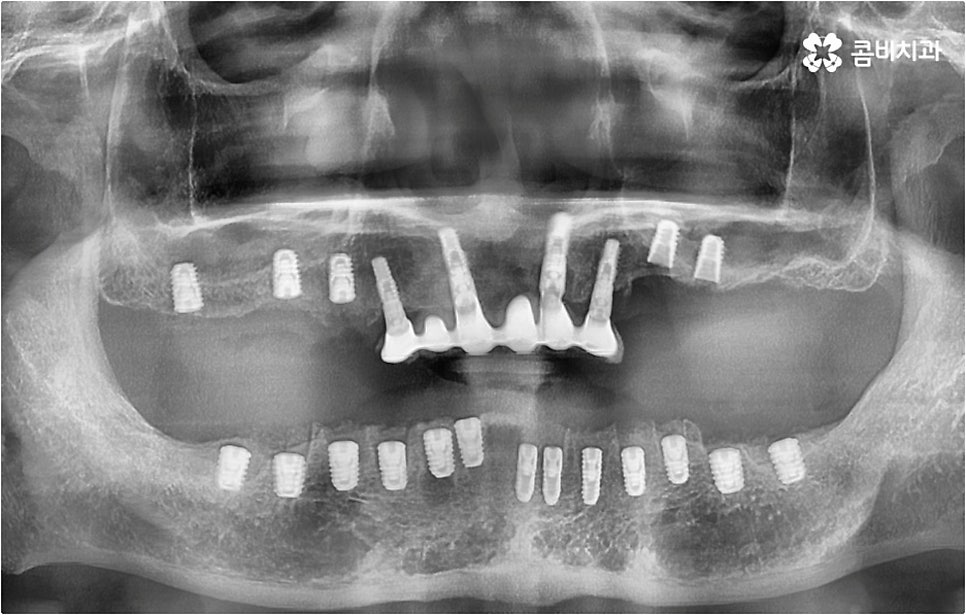

아무 것도 없는 상태에서 제대로 저작 기능을 발휘할 수 있도록 다시 구강 내부를 재현하는 전악임플란트 는 굉장히 고난도에 속하는 치료이기 때문에 충분한 임상 경험을 가지고 있는 숙련된 의료진과 함께 하실 필요가 있어요. 전악임플란트 방식이 빠진 영구치 자리마다 다 임플란트를 식립하는 것이 아니라, 상하악 각각에 8~12개 정도로 필요한 최소한의 인공 치근을 심고 그 사이 사이는 브릿지 방식으로 보철물을 연결하는 것이기 때문에 저작력을 골고루 분담하여 안정적인 지속성을 높일 수 있도록 환자 개개인의 상태에 맞게 인공 치근의 위치, 각도, 간격, 심는 깊이 등을 세밀하게 설정하여 교합을 제대로 맞출 수 있는 시술자의 뛰어난 기술력과 풍부한 노하우가 요구되는 거예요.

또한 이를 위해서 치아 주변 조직과의 거리나 잇몸뼈 높이, 밀도 등을 정확하게 파악할 수 있도록 도와주는 3D CT와 같은 정밀 진단 장비를 갖추고 환자분들의 상황에 맞는 계획을 세워 무리하지 않게 진행할 수 있는 체계적인 시스템을 운용하는 치과에서 임플란트 시술을 받으실 필요가 있어요. 만약 치과내 자체 기공소를 갖추고 있다면 보철물 제작에 대한 피드백이 보다 빠르게 전달, 반영될 수 있어 환자분들이 이용하시기에 좀 더 편안하실 거예요.